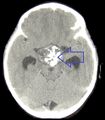

في بعض الحالات ، يمكن أن يساعد ماسح التصوير بالرنين المغناطيسي القوي 3T (Tesla) في تحديد موقع هياكل الدماغ الهامة المتأثرة بالورم. يتكون النمط النسيجي من تعشيش ظهارة حرشفية تحدها خلايا مرتبة بشكل اشعاعي. غالبًا ما يكون مصحوبًا بترسب الكالسيوم وقد يكون له بنية حليمية مجهرية. يعد التصوير المقطعي المحوسب (CT) أيضًا أداة تشخيصية جيدة ، حيث يكتشف التكلس في الورم..[20]

في النوع المينائي ، تظهر التكلسات في التصوير العصبي وهي مفيدة في التشخيص.

يظهر التصوير المقطعي المحوسب ورم قحفي بلعومي